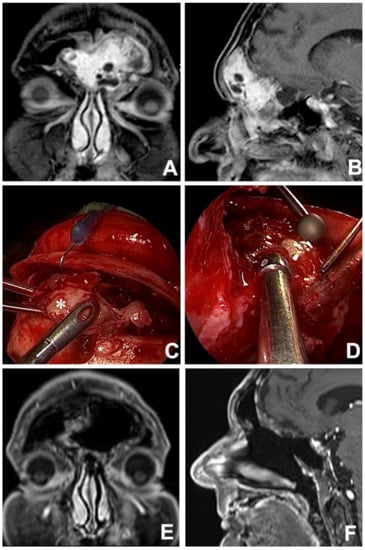

Figure 5. Preoperative MRI in coronal (A) and sagittal (B) views showing a frontoethmoidal neoplasm with massive bilateral frontal sinus involvement. After an endoscopic transnasal biopsy, the lesion was histologically defined as biphenotypic sinonasal sarcoma. The lesion (*) was resected via a combined surgical approach: frontal sinus osteoplastic flap (C) and endoscopic transnasal approach (D), achieving free resection margins. A contrast-enhanced coronal (E) and sagittal (F) MRI performed 2 years after treatment proved no evidence of residual disease and ruled out local recurrences.

Among rhinologists, the frontal sinus is recognized to be one the most challenging areas to reach surgically and, even nowadays, external approaches might be needed to manage specific situations (Figure 4) [62]. Over the years, instrumental and technological evolutions have allowed the application of minimally-invasive endoscopic approaches in the management of frontal disease, even in the case of malignant tumors. Currently, endoscopic transnasal and external approaches (i.e., transcranial/transfacial) should be considered as complementary techniques that must be mastered by the skull base surgeon, who must be able to switch from endonasal to external procedures whenever required, depending on intraoperative findings (Figure 5).